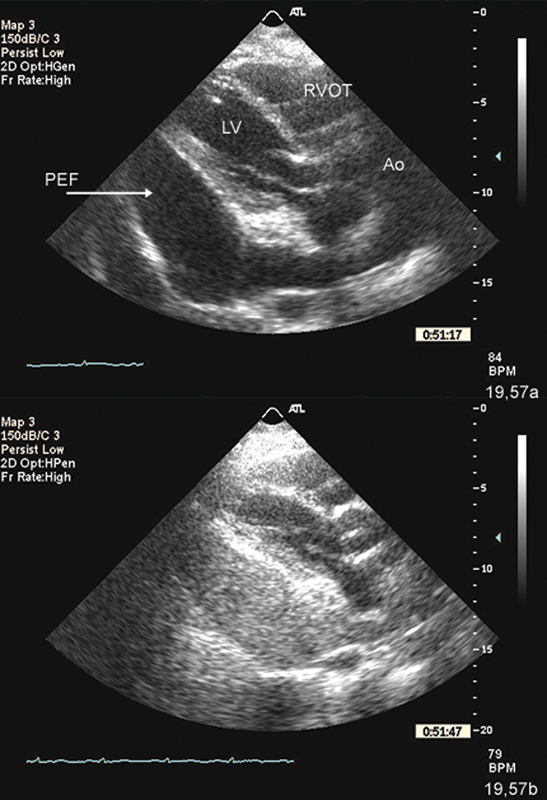

فحوصات تشخيصية لبعض امراض القلب والشرايين التاجية